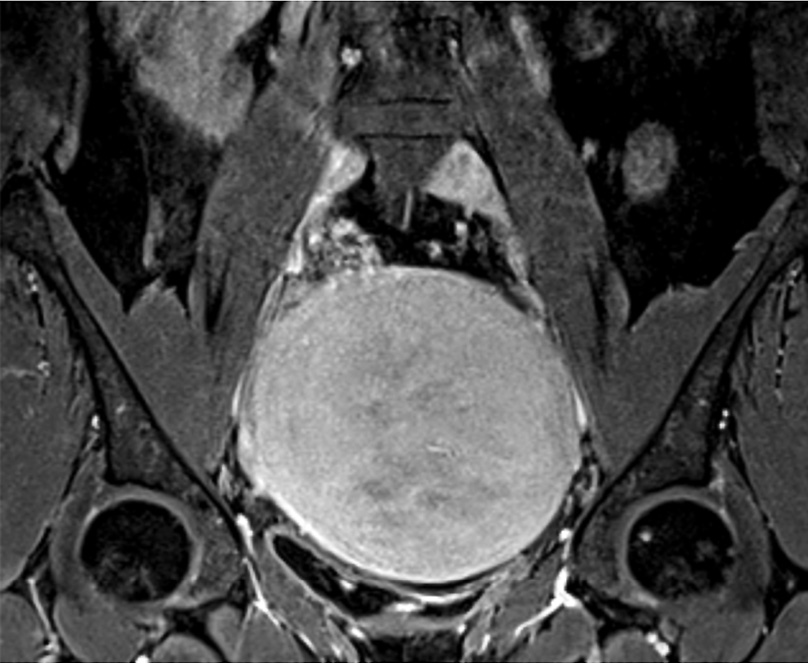

При поступлении пациентке проведено МРТ органов малого таза с контрастированием (рис. 7): матка увеличена до 122×98×107 мм за счет массивного шаровидного миоматозного узла по передней стенке до 89 мм в диаметре. Правый яичник расположен над маткой, общим размером 24×14×30 мм, его структура гомогенная, фолликулярный аппарат выражен слабо, с наличием немногочисленных мелкокистозных включений до 5 мм в диаметре. Левый яичник расположен в задних отделах таза над маткой, общим размером 23×19×28 мм, фолликулярный аппарат выражен слабо, с наличием немногочисленных мелкокистозных включений до 5 мм в диаметре. При оценке DWI/ADC – без особенностей.

Рис. 7. Клинический пример №2. МРТ с контрастированием до проведения ЭМА. / Fig. 7. Clinical case 2. Contrast-enhanced MRI before UAE.